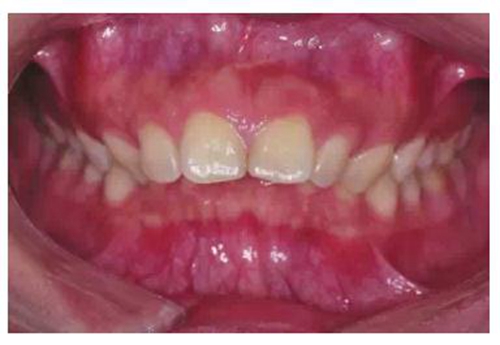

由于有很多患者在微笑時“頰廊”會比較明顯(圖2),這種情況往往預示著其上牙弓狹窄或上頜后牙過于舌傾(圖3),從而影響了微笑的美觀,正畸時有必要直立上頜后牙,這樣就可以創(chuàng)造飽滿的微笑,這類病例可以考慮選擇上頜前磨牙的零度轉矩,有效實現(xiàn)上頜后牙的直立。

圖2 患者在微笑時“頰廊”

圖3 存在“頰廊”者的口內情況